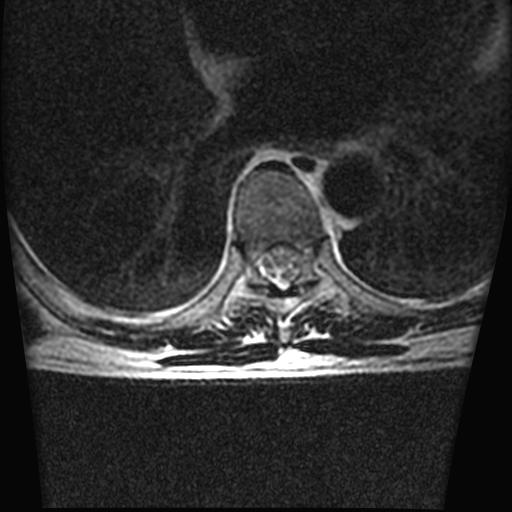

标题: MRI0985:胸椎.68岁男性,胸部疼痛,

68岁男性,胸部疼痛,不适。

胸7椎体楔状变形及信号异常,附件未见明显异常信号.椎间隙正常.未见软组织块影.考虑骨质疏松所致压缩性骨折可能大.

胸7椎体楔状变形及信号异常[t1t2 均为低信号],附件未见明显异常信号.椎间隙正常.未见软组织块影.考虑陈旧性压缩性骨折伴退变。

首先需除外单发成骨性转移瘤可能。

转移瘤也不能排除